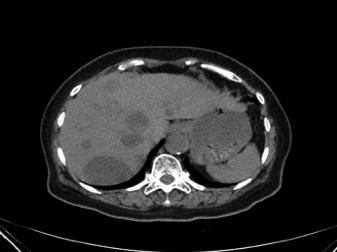

患者头皮包块较前明显缩小,溃疡面已结痂,无渗液及渗血。复查腹部CT示肝脏多发低密度灶,考虑肿瘤性病变可能,肝右前叶病灶合并少许出血,和治疗前旧片比较病灶增多、增大。

2017-3-1